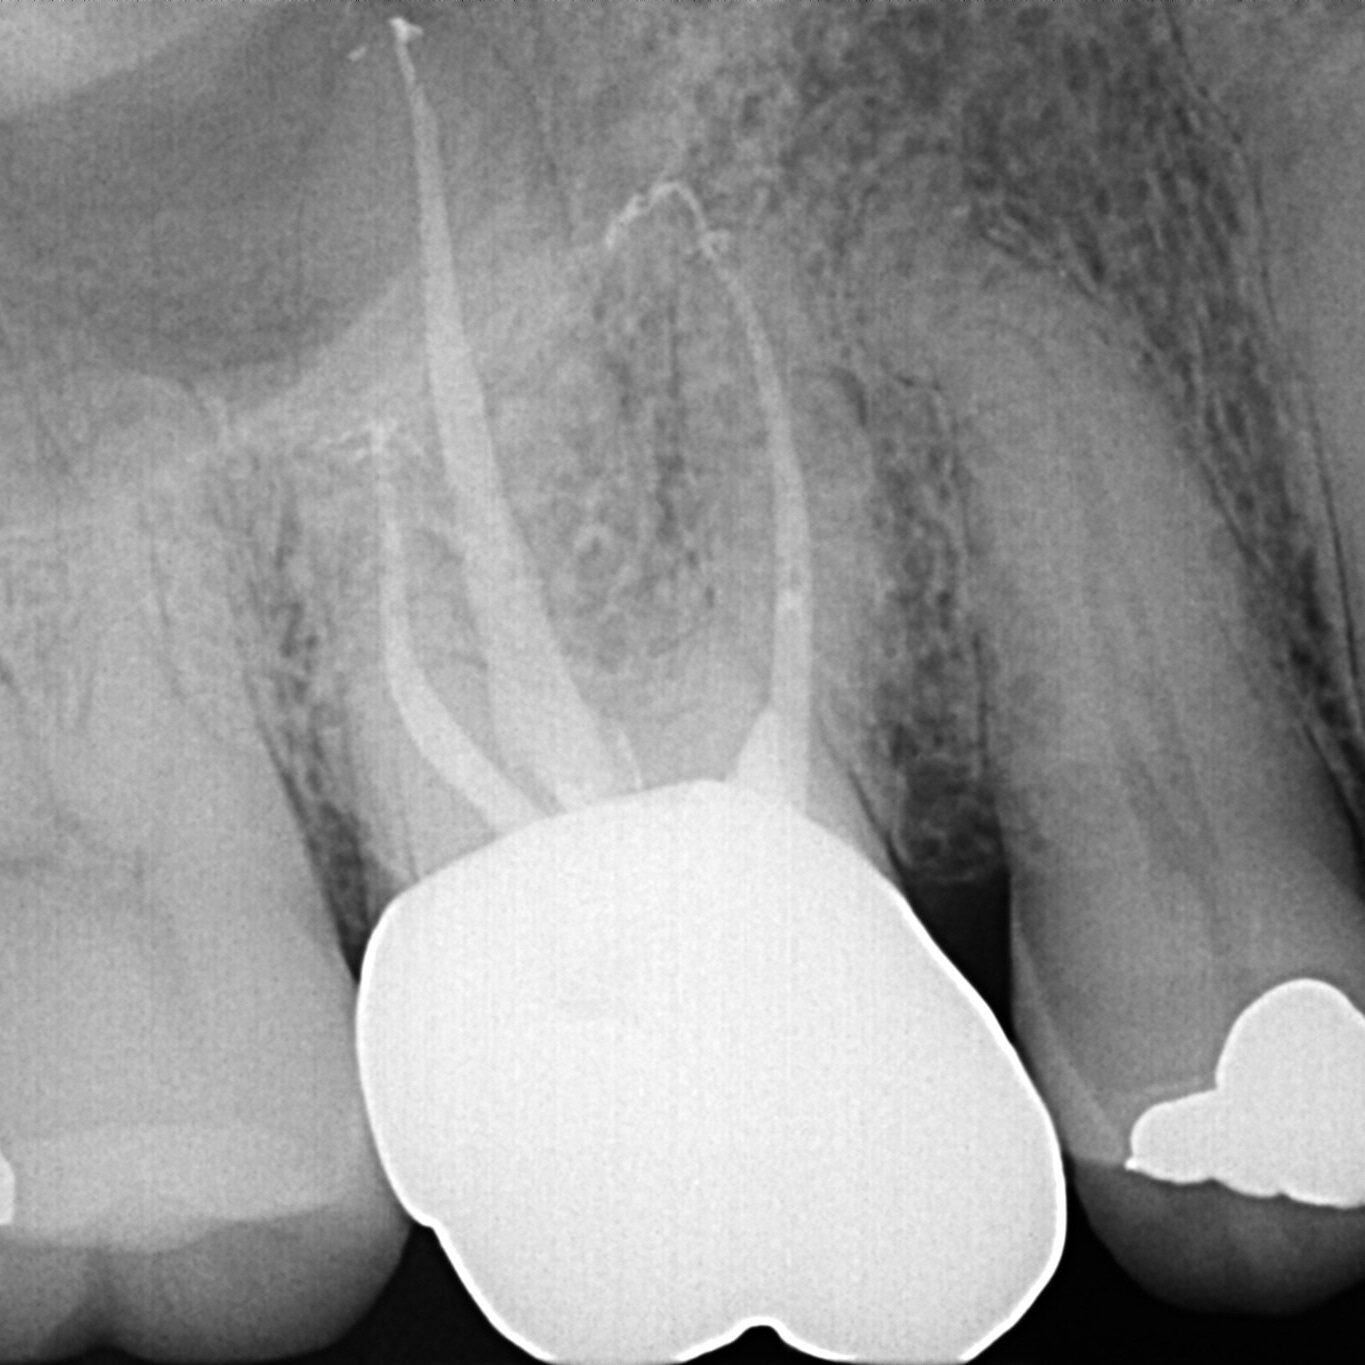

Patient was referred for a Root Canal Treatment #3. Diagnosis: PN/SAP. Access prep completed. Orifice opening completed with ProTaper Universal SX. While scouting for WL, a .10 hand file separated in the MB1 canal. The tip was near the junction with MB2, and the separation occurred near the orifice. Sponge and Cavit placed and new radiograph made. Ultrasonics used to trough around file mostly lingual to the instrument, using the MB2 canal as a guide until the MB2 canal joined the MB1. Doing this, tooth structure palatal to the file was removed and very little tooth structure along the outer edges of the canal system required removal. During this process, about 3mm of the coronal portion of the file broke and was removed. At this point, I switched to the TFRK ultrasonics and continued until 2-3mm of the file was exposed and there was some mobility present. EndoCowboy 0.12mm used to lasso the file. File removed in its entirety without complication. Case completed without further complication. No additional visit necessary. Post-op PA showed minimal loss of tooth structure required for file removal.

Without question, the TFRK ultrasonics and the EndoCowboy are the best tools currently available for dealing with unforeseen complications during endodontic treatment. From visualization and negotiation of deep bifurcations to removal of separated instruments, PlanB Dental provides the tools to treat cases confidently and efficiently. With the TFRK ultrasonics and the EndoCowboy in hand, I no longer feel limited by my equipment. When a separated file is present and I can see it, I can remove it!